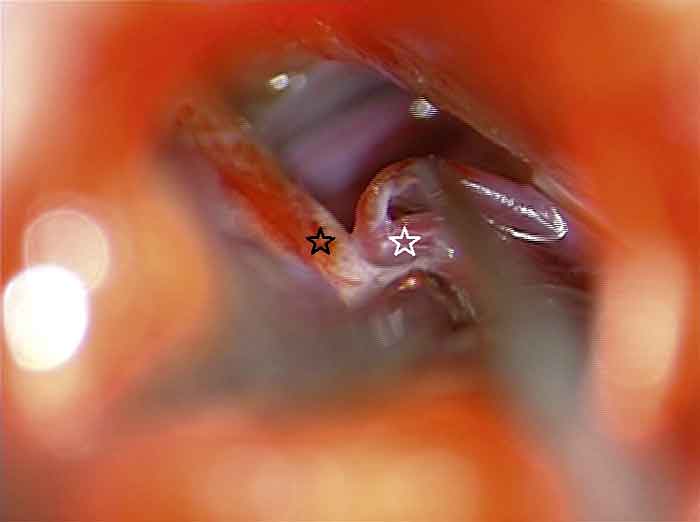

De kirurgiska behandlingsmetoderna indelas i destruerande och icke-destruerande. Den icke-destruerande kirurgin representeras av mikrovaskulär dekompression, som innebär att trigeminusnervens rot dekomprimeras från ett blodkärl som trycker på den vid inträdet till hjärnstammen i förekommande fall. Den destruerande kirurgin består av

Operationsområdet sett genom operationsmikroskop. Arteria cerebelli superior (vit stjärna) komprimerar trigeminusnerven (svart stjärna) vid dess inträde i hjärnstammen. Artären delar sig i två grenar som hålls isär med hjälp av en mikrodissektor.